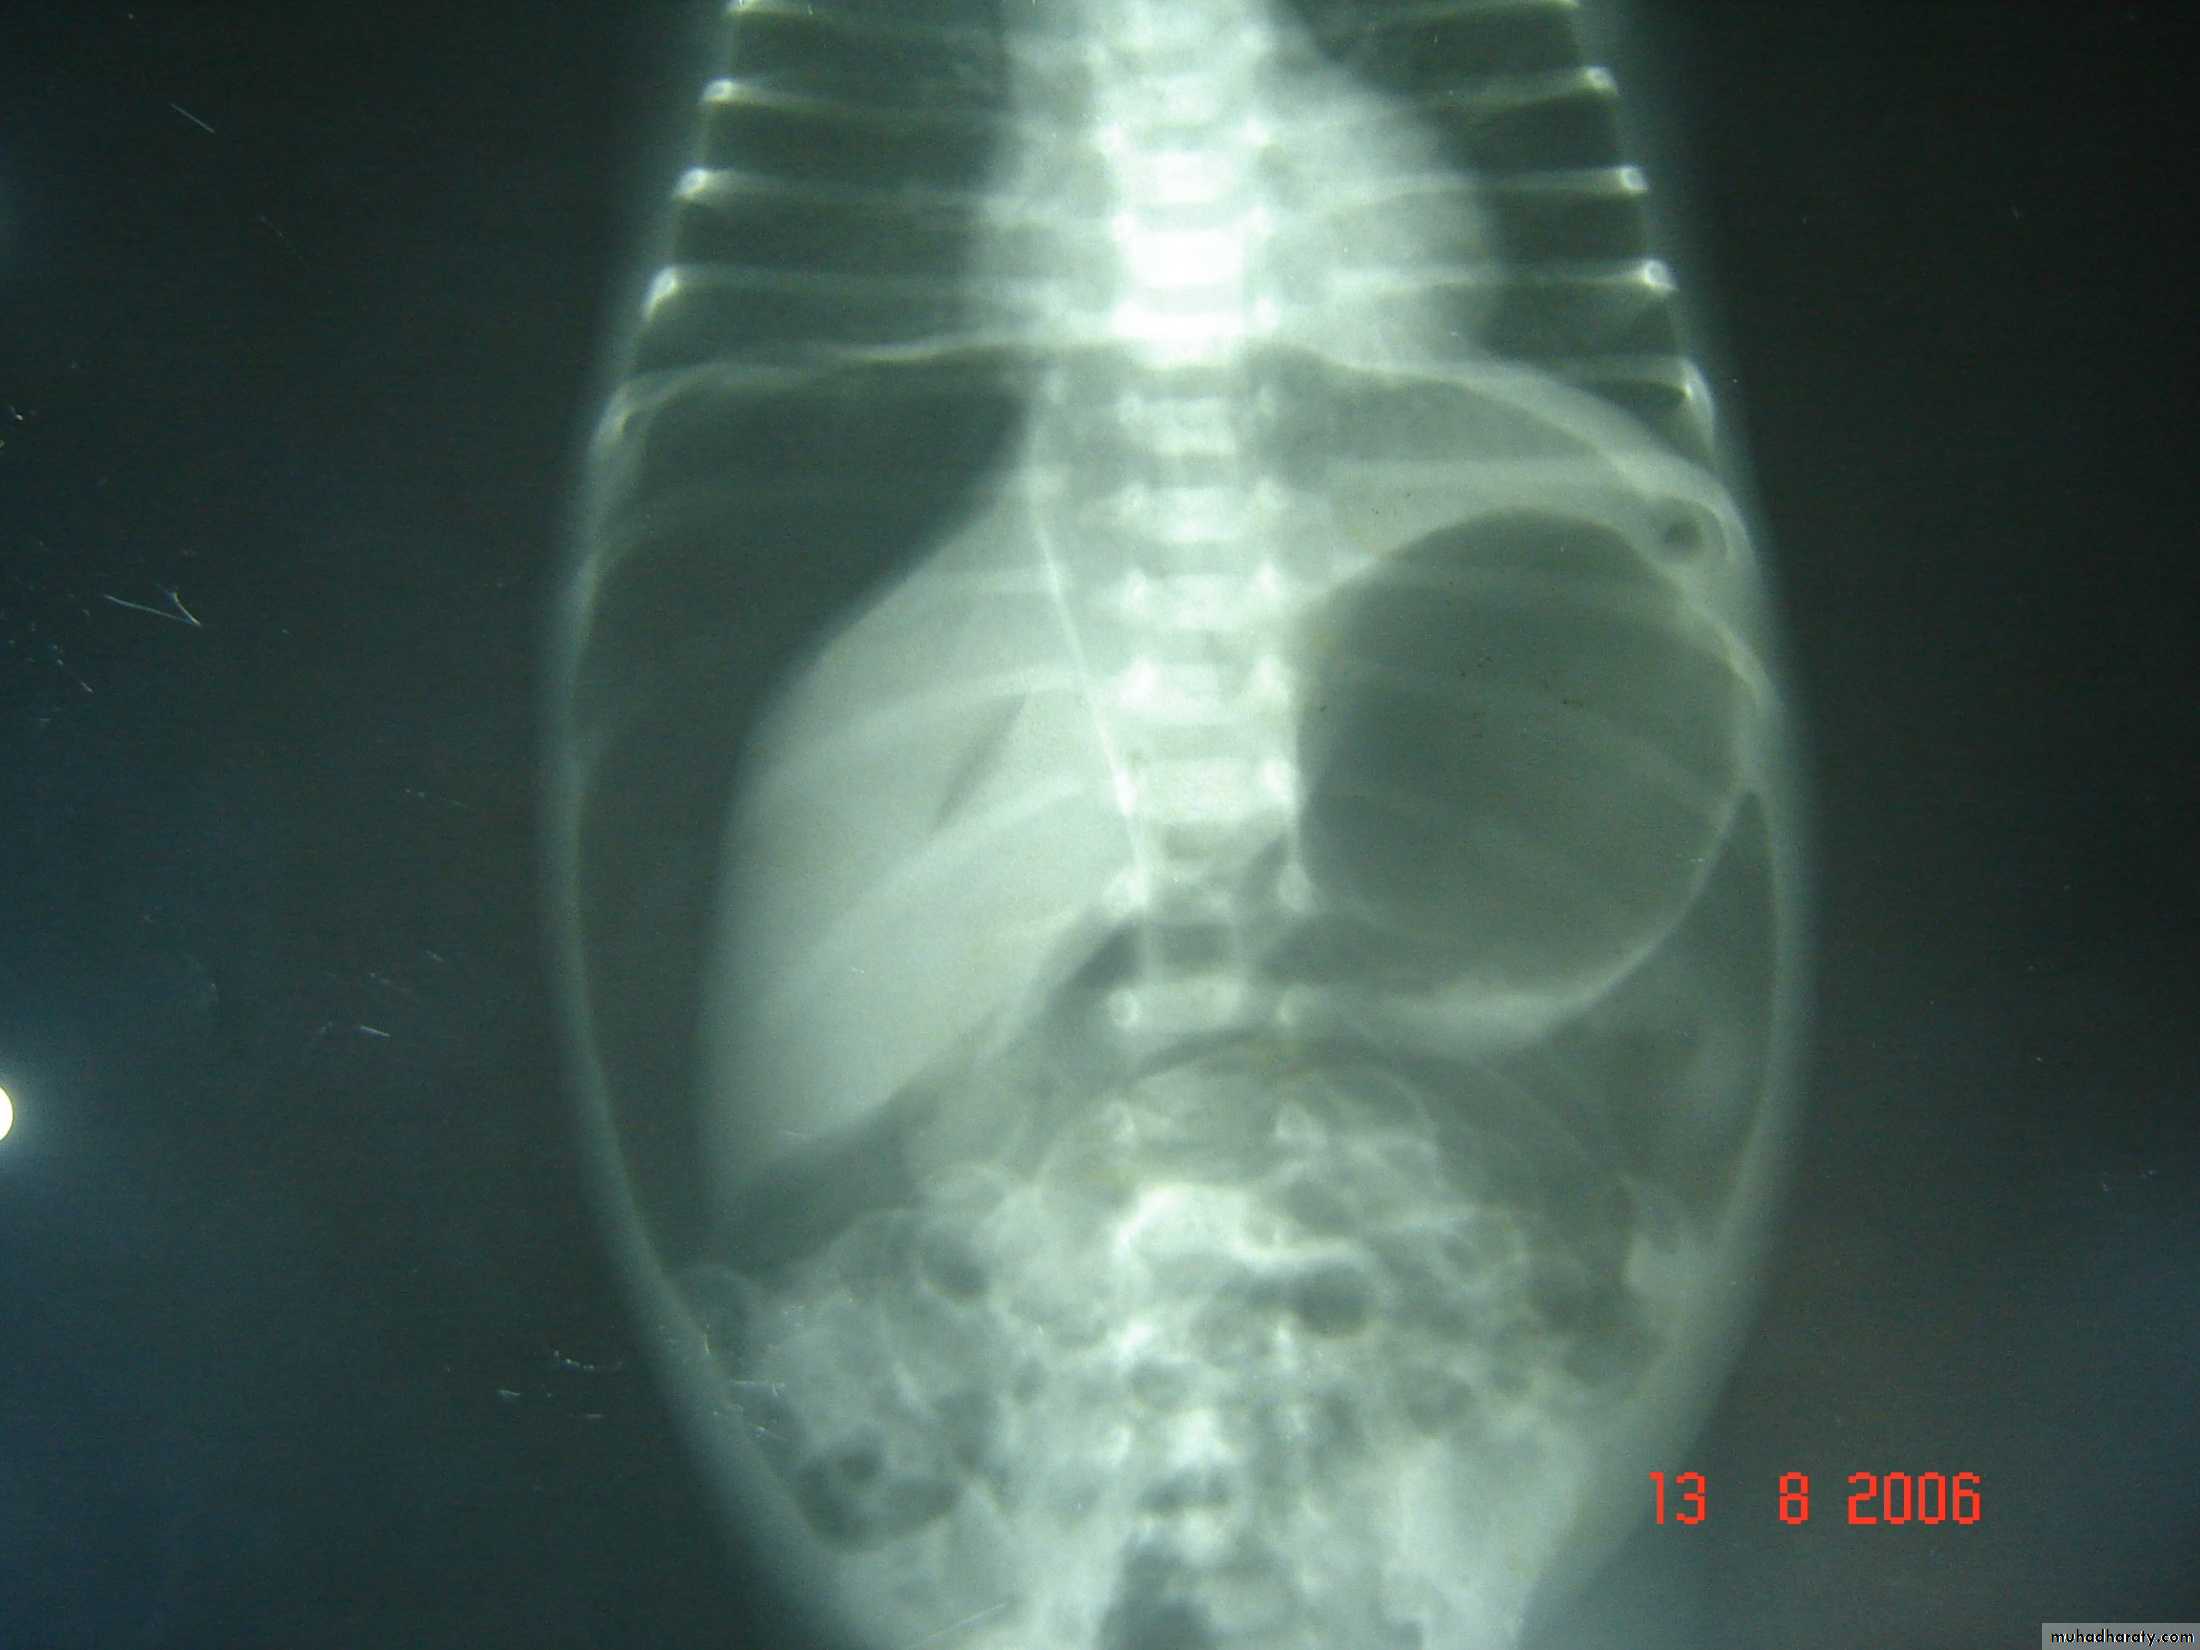

Meconium ileus+atresiaDescription:

• Thick sticky meconium in the ileum.• Signs of abdominal onstruction

• Abdominal duffy (مثل العجبي) mass

• No A/F level in x-ray

• Causes: cystic fibrosis

• Treatment: surgery by excision and re-anastomosis

• Before sugary do gasrtographine enema it could treat the condition

Description:

• Small bowel atresia• X-ray show multiple A/F level

• Treated by surgery resection with end to end anastomosis